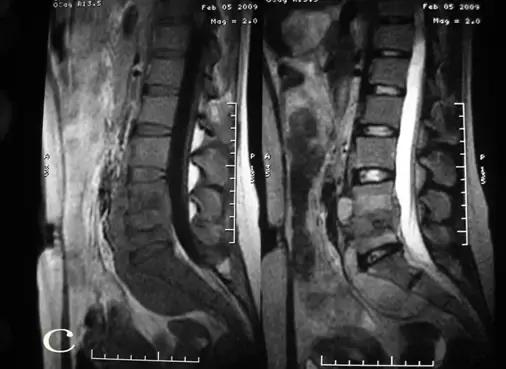

患者郭某,女性,25岁。因腰痛一年余,曾经在多家医院就诊,诊断为腰椎间盘突出,给予对症治疗,当时有所减轻,近来腰痛加重,经检查后考虑腰椎结核而到我院就诊。查体:脊柱向右侧弯曲,L4-5棘间压痛,叩击痛。左侧腹股沟区可触及100px×125px包块,触之波动感。实验室检查:血清抗结核阳性,血沉69mm/h,C-反应蛋白164.9mg/dl,PPD试验强阳性。腰椎平片(图a)示:腰4/5间隙变窄,L4椎体上缘骨质破坏。腰椎CT(图b)示:L4、L5椎体骨质有破坏,并有死骨形成,双侧腰大肌内可见液性暗区。腰椎MRI(图c)示:椎间盘等T1略短T2信号,临近骨组织呈长T1长T2信号,正常椎间盘信号消失,L4椎体下半部分L5上半部分骨质破坏,周围软组织肿胀,腰椎双侧腰大肌及骶前脓肿形成。入院诊断:腰椎结核(L4/5),腰大肌脓肿(双侧),骶前脓肿。入院后给予H.R.Z.E初治方案,同时在CT引导下行双侧腰大肌脓肿穿刺置管引流术(图d),引流后病人症状明显缓解,血沉(36mm/h)、C-反应蛋白(97.9mg/dl)明显下降,复查腰椎CT(图e)脓肿明显减少,经过抗结核治疗四周后给予行后路椎弓根钉棒系统内固定、前路病灶清除取髂骨植骨融合术(图f、g)。

MRI检查(图c)可以早期对脊柱结核进行诊断。可见椎体破坏以椎体前中部为主,T1WI病变椎体呈低信号, T2WI骨质破坏区呈不均匀高信号。伴有骨髓炎性水肿时,炎性水肿区T1WI呈等信号, T2WI呈高信号。椎间盘改变表现在椎间隙变窄,椎间盘受累破坏。T1WI均呈低信号,T2WI信号增高T1WI呈等信号, T2WI呈高信号。周围冷脓肿表现,T1WI呈中等低信号, T2WI呈中等高信号,脓肿多位于破坏椎体前后方及两侧,略呈梭形范围较广泛。